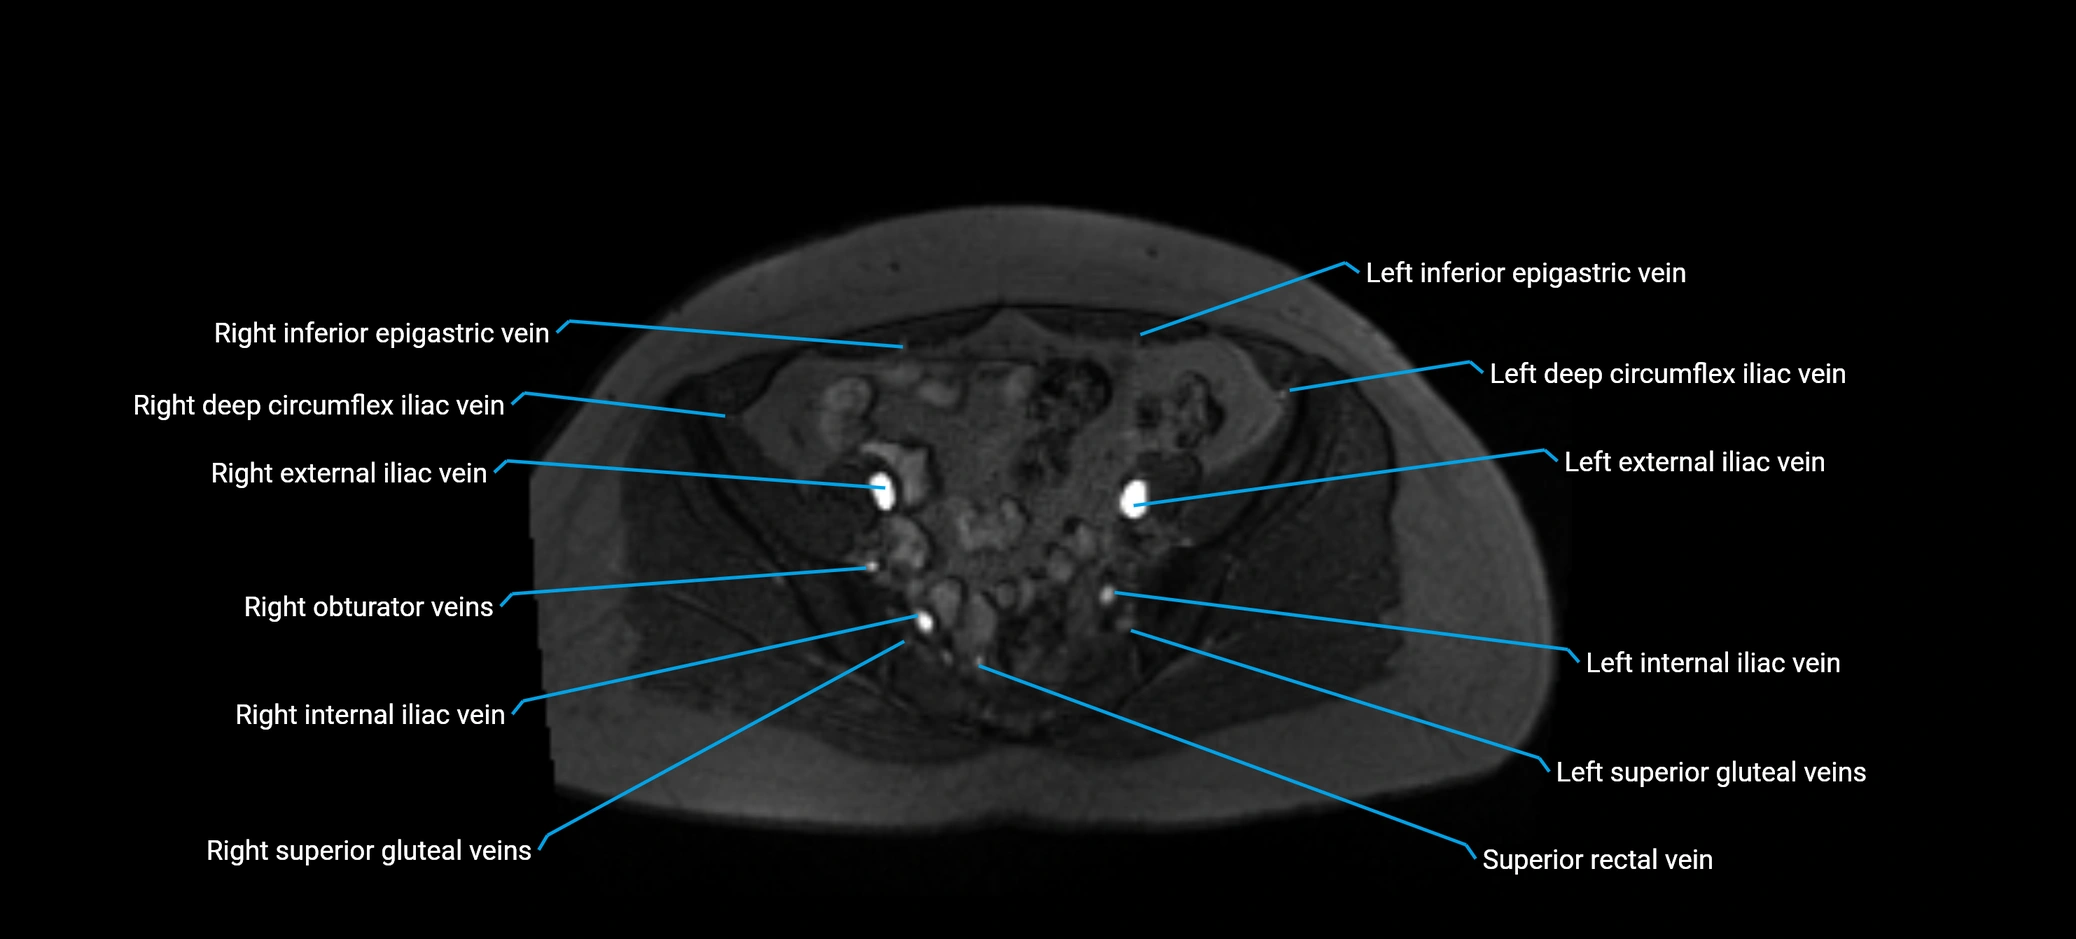

MRI image

image